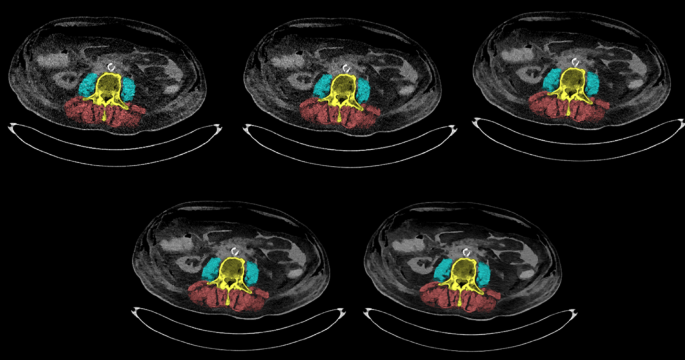

Muscle area and density were measured on a single slice in axial plane in the 12th thoracic vertebra and 1st to 4th lumbar vertebra, on the level were both transverse processes were shown. Density assessment relied on the standard CT calibration (with water equaling 0 HU and air − 1000 HU), with scans exported in DICOM format preserving all raw voxel attenuation values. Muscle measurements were performed using Sarcomeas v1.0, software developed in-house (UMCG, The Netherlands). This software facilitates the manual delineation of skeletal muscle areas based on tissue attenuation values obtained from the calibrated CT data preserved in the DICOM files14. Within these outlines, skeletal muscle was defined as all voxels with a radiodensity within the range of -29 HU to + 150 HU, while for adipose tissue was defined within the range of -190 HU to -30 HU15. The mean muscle density in HU was calculated by averaging the density of all voxels within the delineated muscle area that fell within the specified range for muscle tissue. All muscle contours were delineated on the default scan by an experienced board certified musculoskeletal radiologist with 15 years of experience (A.V.) and included the erector spinae, quadratus lumborum and psoas major muscles (Fig. 1). We excluded ventral abdominal wall muscles from delineation, as they were not fully intact due to prior surgical training procedures. To avoid bias from variation in manual delineation, all contours in the default scan were copied to the scans with the other parameters. For each vertebral level and body, the calculated values were summed and averaged, resulting in 30 measurements of muscle area and 30 measurements of muscle density per individual technical CT parameter.

We used human bodies which have been embalmed by the method as first described by Walter Thiel11,12. To our knowledge, no studies have specifically examined differences in X-ray attenuation between living patients and Thiel-embalmed bodies. Given that our measured HU values are similar to those of living patients, we expect that tissue attenuation in Thiel-embalmed bodies is consistent with that of living tissue, thereby minimizing any substantial bias. In our institution these bodies serve primarily for surgical training purposes. In the abdominal area they are mainly being used for intraperitoneal procedures, both laparoscopy as laparotomy (e.g. body in Fig. 1 has intra-abdominal air due to recent laparoscopy training). Consequently, the muscles of the ventral abdominal wall were not fully intact. Thus to prevent bias we decided to only delineate the psoas, erector spinae and quadratus lumborum muscles.